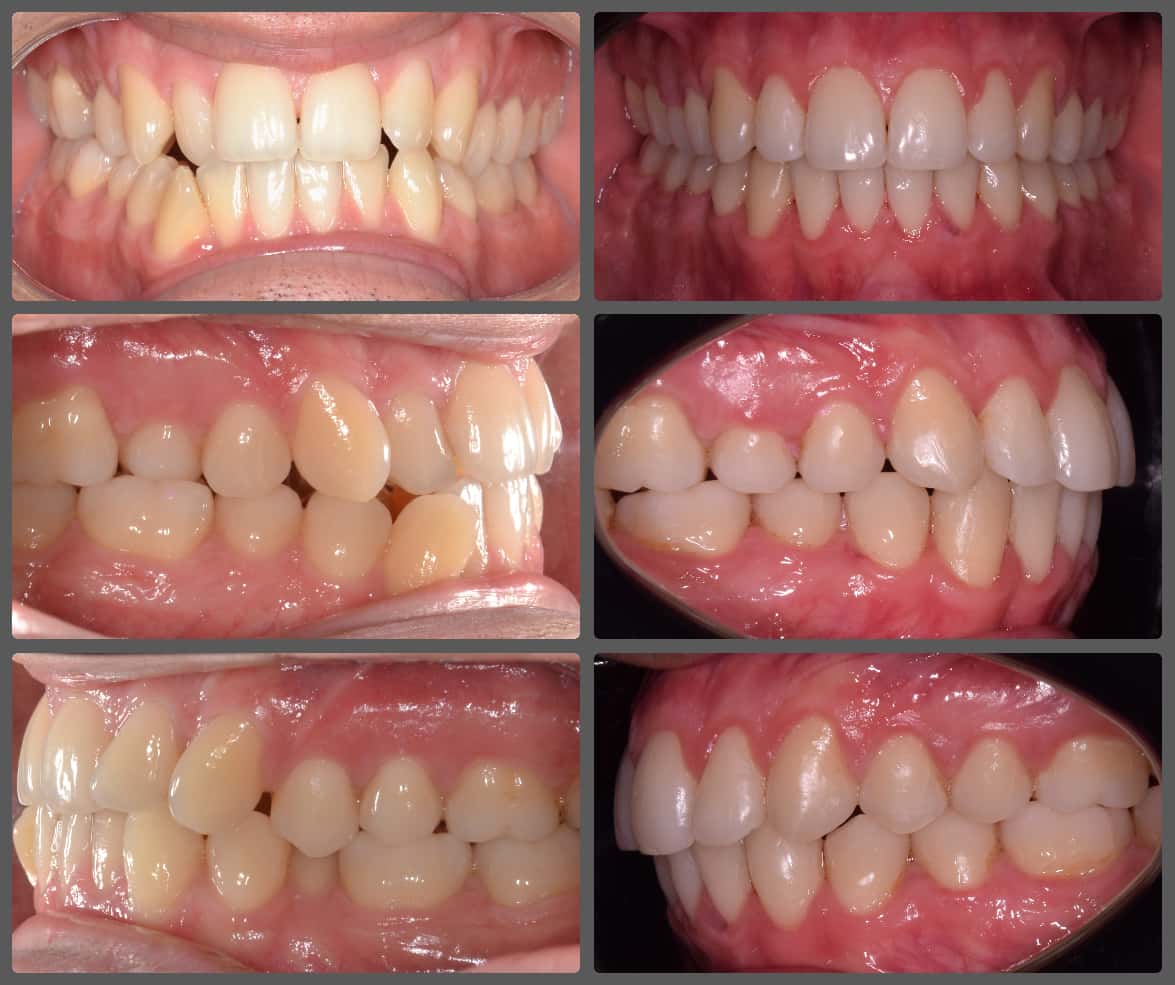

Balázs súlyos alsó torlódása miatt keresett fel magánrendelésemen. A diagnosztikus vizsgálatok során előbbin túl alsó-felső fogívszűkületet, valamint nyitott harapási hajlamot állapítottam meg. Kezelését Pitts21 alsó-felső rögzített fogszabályozó készülékkel kezdtük meg. A nyitott harapási hajlamot a hátsó fogakra helyezett harapásemelővel kontrolláltuk. A torlódott fogaknak tolórugóval és interproximális redukcióval teremtettünk helyet, és intermaxilláris gumihúzással tökéletesítettük a harapást. A fogszabályzó kezelés teljes időtartama alatt Balázs 110%-osan együttműködő volt, ezért 21 hónap alatt sikerült kiemelkedő végeredményt elérnünk.